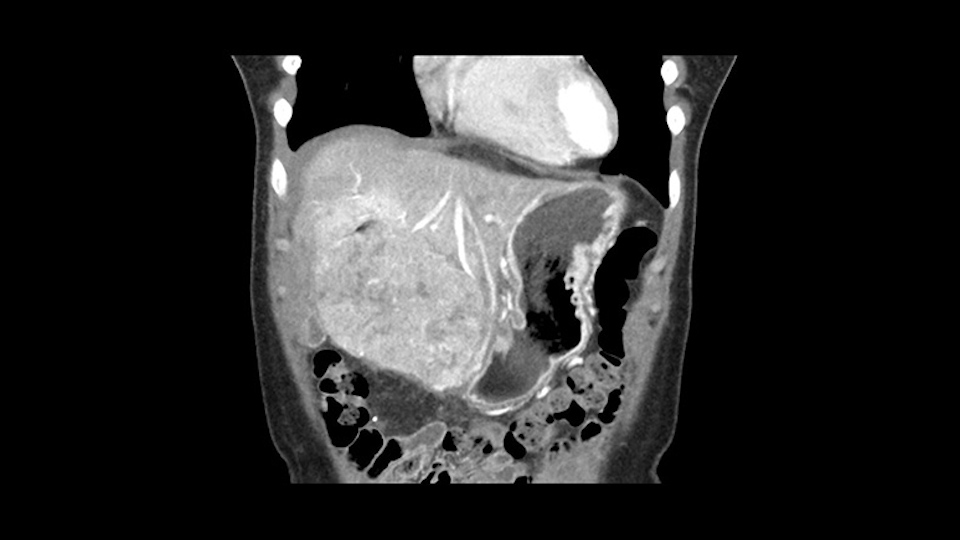

So if we look at the CT scan, on the axial, it’s a larger lesion. It’s about 6 or 7 or 8 centimeters. So it does look a bit threatening in terms of its resectability but if you really drill down deeply into the anatomy, and I think the coronal [imaging] is even better, you can see that the entire mass is on the patient’s left side of the falciform ligament. So it’s really only a left-sided tumor and not even really a left-sided tumor because Segment 4 is uninvolved anatomically.

As I review the CT scan, we have both arterial and venous phases, the tumor is obvious. But I’ll start by saying that the liver itself does not appear to be cirrhotic to my eye. It’s got a normal contour and allied to that, that I do not see evidence of portal hypertension. The spleen is normal, there’s no collateral vessels. The tumor itself, I measured maximally at about 11 centimetres in diameter and I’m told the alpha fetoprotein is very high (over 10000), which is entirely consistent with this being a solitary hepatocellular carcinoma that is very exophytic. It seems to emanate off the inferior margin of Segment 3 (because that’s the falciform). I’ll start by saying that this is not transplantable. The tumor exceeds our guidelines for transplantation, but it's likely resectable based on normal liver and no portal hypertension.

So the issue with regards to resection. A left sided tumor. I believe I can see the falciform ligament right here so we’re looking at a resection of Segments 2, 3 of the left lobe of the liver. The left portal vein is right there. I think we’ll be wiser to take the left portal vein and therefore get well into Segment 4 and do a left hemihepatectomy. Certainly, one does not need to take the middle hepatic vein; it’s miles from the tumor.

Hi my name is Sedat Karademir. I’m from Ankara Guven Hospital and I’m an HPB and transplant surgeon. We are discussing about the case I reviewed the CT of 41 year old lady with a suspected hepatoma in the left lateral segment. Presumably its Segment 3. It looks like a big tumor sitting exophytically mostly out of the liver and pressing on the surrounding organs, but it doesn’t look like any invasion there. In this situation, according to the venous and arterial anatomy, it looks like this will be a Segment 2 and 3 resection.

When you see the axial sections of the scan, you find it's a largely exophytic mass and its well-encapsulated. So this is typically true of a well-differentiated hepatocellular carcinoma. If you look at this, this is the gallbladder which is being displaced to the right and the mass is in the Sg4 of the liver, exophytic, projecting down. As it is coming down, it is also displacing the duodenum and the head of the pancreas which is being pushed towards the left and it's going right up to the cava, the start of the anterior surface of the cava. Obviously getting a lot of collaterals and vascularity from all the vessels around but one has to be very careful in evaluation of the main portal pedicle in this particular case and of course arterial inflow to the Sg4 and of course the left lobe of the liver.

My name is Gonzalo Sapisochin. I’m an assistant professor of surgery at the University of Toronto and a hepatobiliary and pancreatic surgical oncologist here at the University Health Network. So this patient has a big mass, likely growing from the left lobe of the liver, around 9-10 cm.

So in planning for this operation, as I look at the scans, I first visualize the arterial phase and I can see that there’s are a lot of big feeding arteries to this large tumor. Likely all the right side vessels feeding the right side of the liver: right hepatic artery and likely the Segment 4 artery are spared from the tumor. It’s likely the left hepatic artery is ramificating and giving feeding arteries to this tumor. It certainly looks like a large mass that its compressing other structures like the cava, the pancreas, the stomach; but I think there’s a plane and we can see that better in the venous phase. There’s a plane of separation between the gallbladder, the pancreas, the cava, that this tumor is abrupting but likely not invading. Usually, these masses actually don’t invade at that level and basically are pushing the tissues and once you open, you’re able to separate the tumor. Sometimes there’s some adhesions but you can actually separate and there’s usually no invasion.

The other thing I would do in this case is to certainly to assess the coronal phase as we can see in the coronal phase, this tumor looks like it's growing from Segment 3, and again I don’t think there’s involvement of the right side of the liver or even on Segment 4.